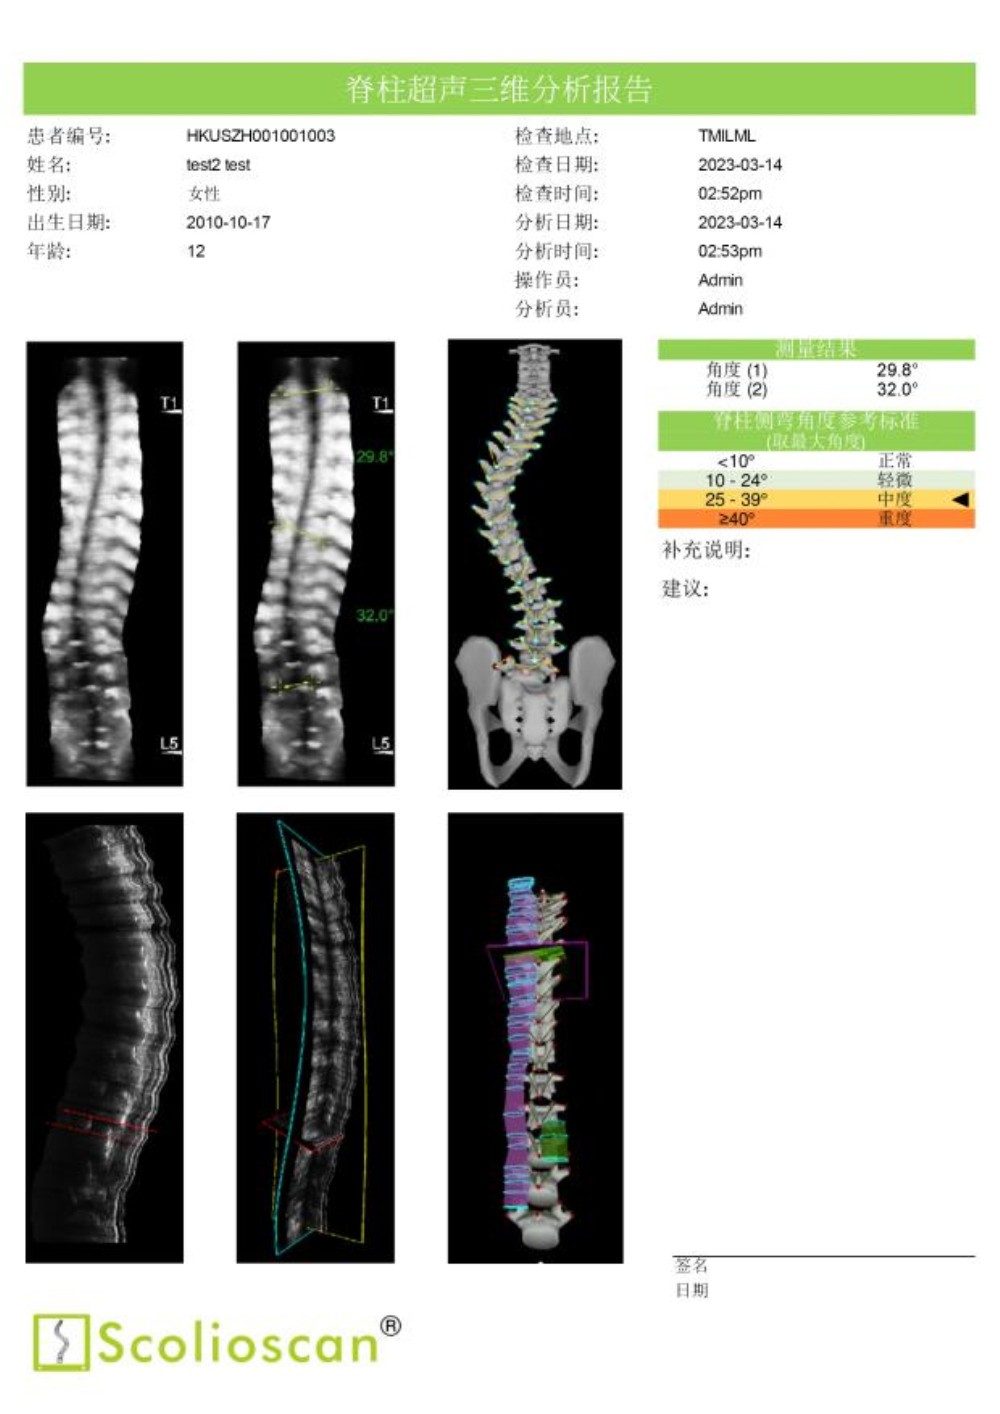

临床试验结果显示,Scolioscan®的测量结果与X光成像高度一致,线性相关度达到0.9464。使用Scolioscan®及早发现青少年的脊柱侧弯问题后,医生得以把握宝贵的黄金治疗时机,通过非手术方式有效控制和治愈疾病,实现早诊断、早治疗、早康复。

通过动态监测侧弯治疗情况,医生能有效帮助孩子选择适合的运动与锻炼方法。密切的超声监测有助于医生在疾病治疗的黄金期积极追踪病情和评估、调整治疗方案,根据脊柱的最新状况,第一时间采用体育运动、手法治疗、支具佩戴等保守疗法为患者矫正,有效减小脊柱侧弯度数。Scolioscan®提供的肌骨三维分析还可以协助医生以关节—肌肉—神经三维度为整体,全面进行脊柱侧弯的综合康复治疗。

内蒙古自治区首台“Scolioscan®无辐射三维超声脊柱侧弯评估系统”成功引入我院,可广泛应用于脊柱侧弯筛查、诊断、病情跟踪和预测以及非手术治疗阶段对治疗结果的可视化反馈和评价等多个领域,为广大儿童青少年提供精准度媲美X光的无辐射、安全的脊柱侧弯评估方案,帮助患有脊柱侧弯的孩子早发现、早干预、早康复,竖起脊梁健康成长。